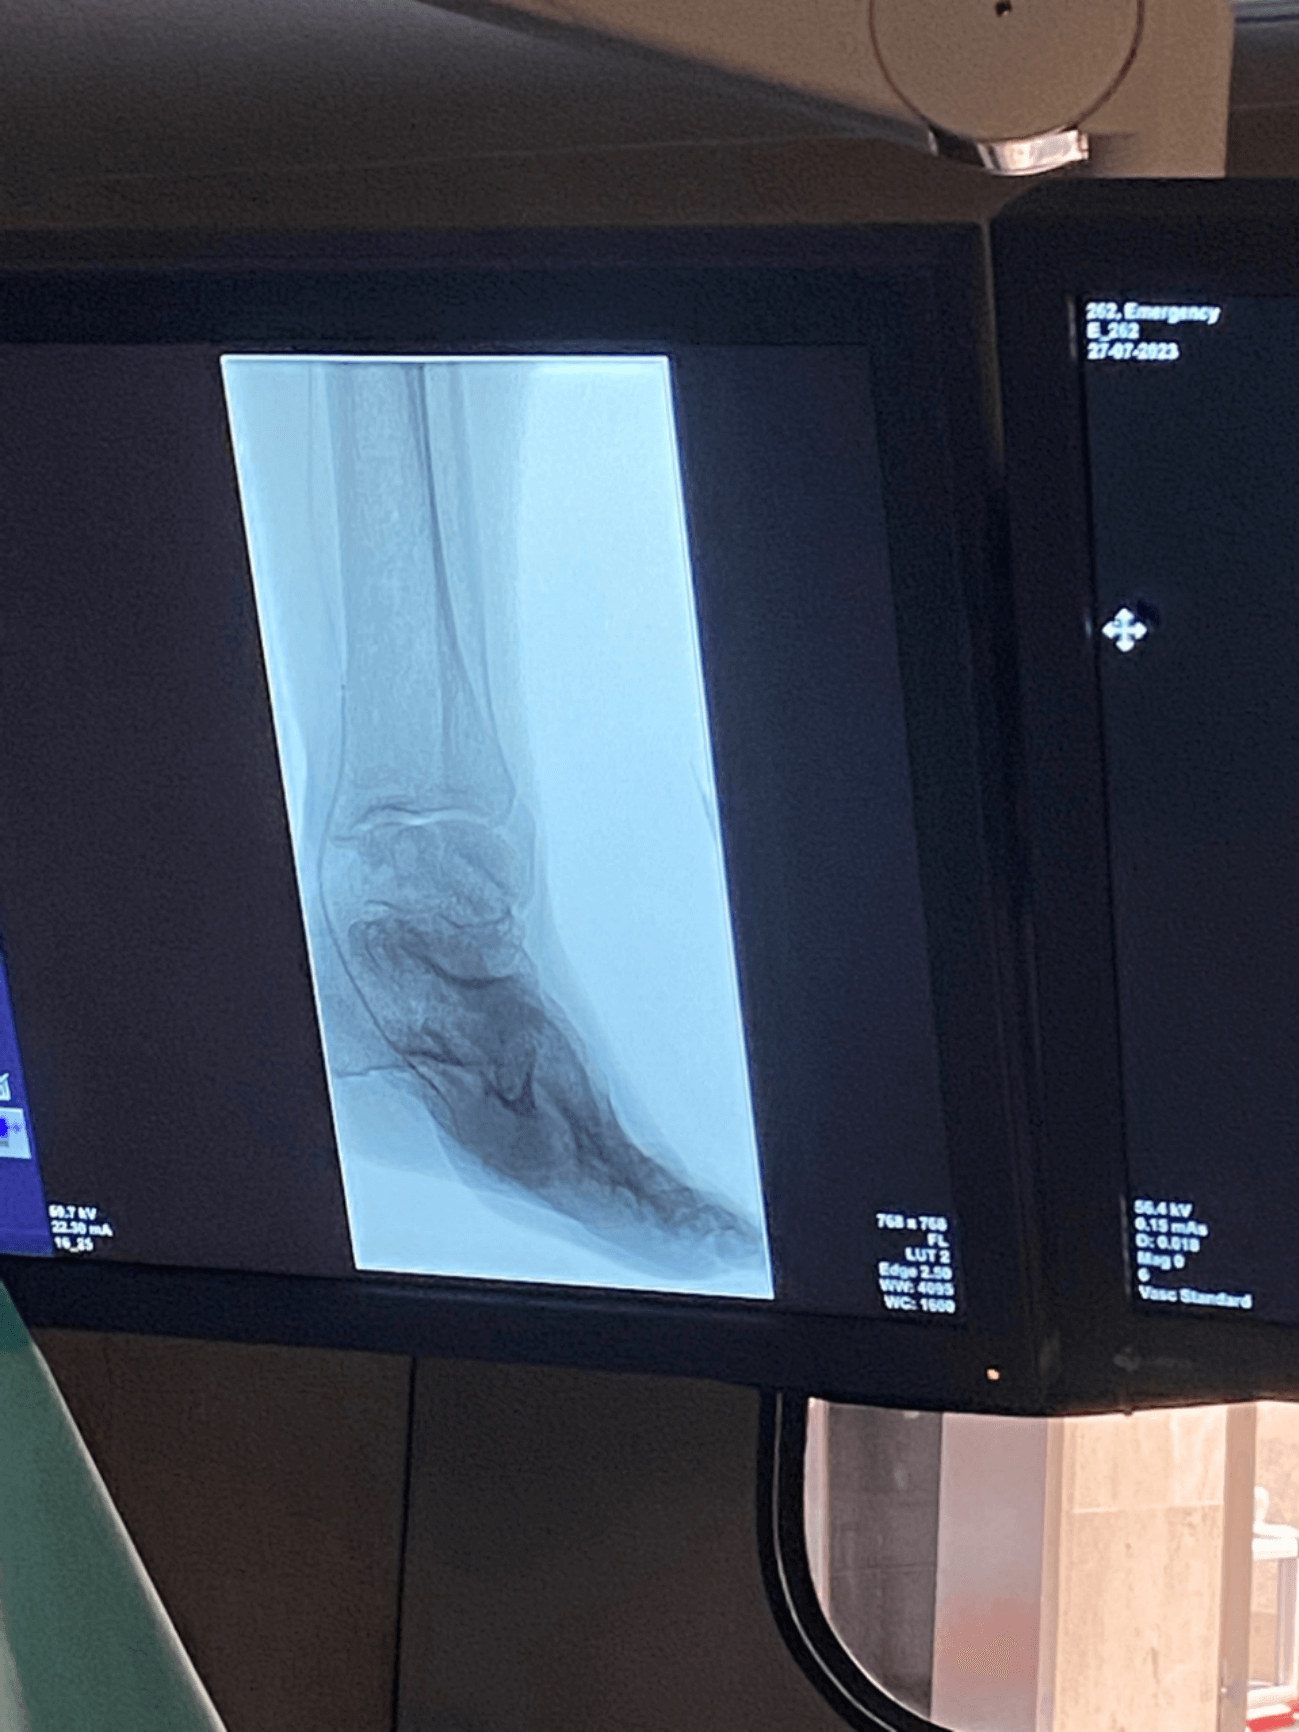

临床图片分享

PTA 0.014” 外周球囊扩张导管